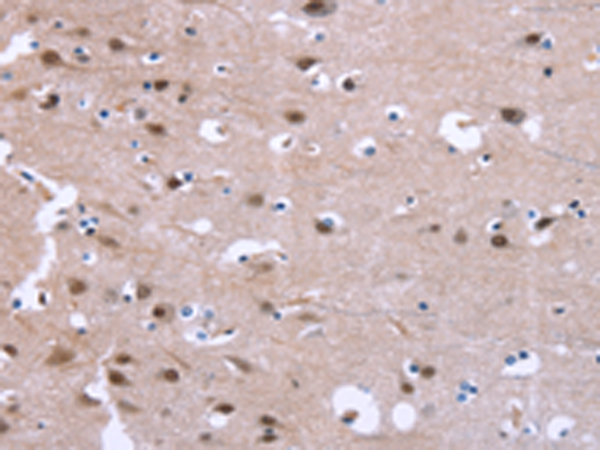

分类: 科研抗体货号: P04889别名: GAT1; GABATR; GABATHG应用: WB,IHC反应种属: Human, Mouse, Rat